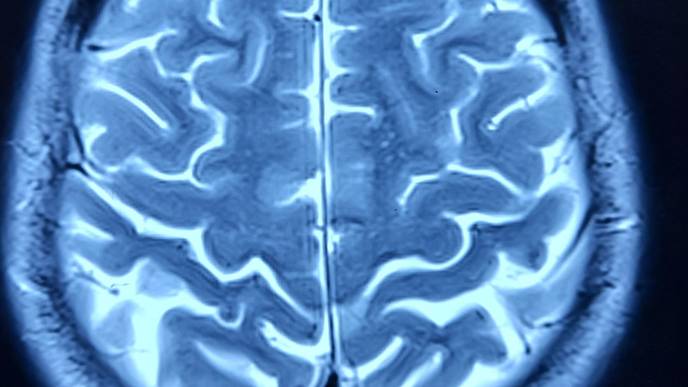

Neuroscientists have long relied on functional magnetic resonance imaging (fMRI) to identify patterns of activity in the brain by measuring changes in blood flow. This has been an invaluable tool for studying brain organization at the individual level.

The deep scanning approach revealed that in a majority of volunteers with depression diagnoses, a brain feature called the salience network is nearly two-fold larger than in controls who didn’t experience clinical depression. The salience network is a group of brain regions in the frontal cortex and striatum thought to be involved in reward processing and determining which stimuli are most worthy of attention.